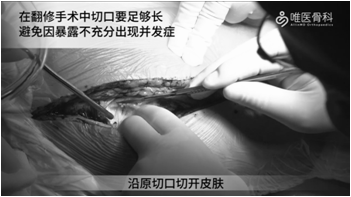

手术显露:沿原切口逐层切开,然后紧贴粗隆分离软组织,并松解臀大肌粗隆止点。切开关节囊,留取关节液培养,关节液检查内容包括关节液常规(白细胞计数、分类)、白细胞酯酶试纸检测,微生物培养(需氧和厌氧)。

注意:在翻修手术中切口要足够长,避免因暴露不充分出现并发症。